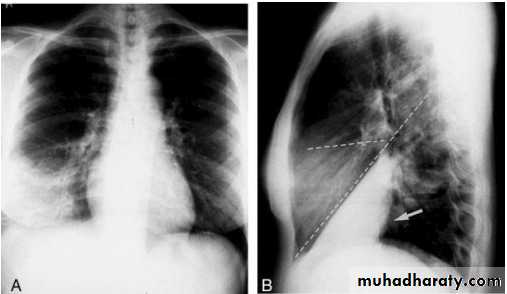

Pleural Effusion on Chest Radiographs.

Posteroanterior (A) and lateral (B) chest radiographs demonstrate the typical meniscoid appearance (arrows) in a patient with a left pleural effusion